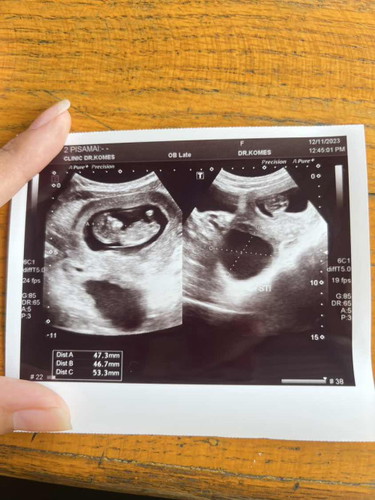

หลังจากน้องลืมของตอนปีใหม่ ยังไม่ถึงปีน้องกลับมาแล้วค่ะ ตอนนี้ 10W+ แล้วค่ะ

เหมือนกันเลย ของเรา ลืมของกลับไปเมื่อ มีนา ตอนนี้กลับมาแล้ว 12วีค แล้วค่ะ ตอนฝาก8วีคหมอก็บอกว่ายังเล็กมากให้เฝ้าระวังตอนนี้ก็ บอกให้ เกาะแน่นๆ มาแล้วก็อยู่ด้วยกันนะ